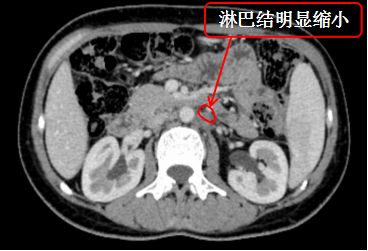

治疗后